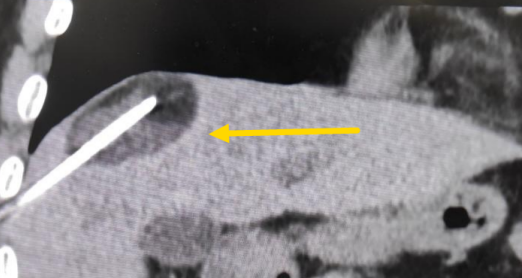

這個患者病變位置刁鉆,穿刺難度大,冷凍消融的難點在于既要不損傷膈肌和肺組織,同時又要盡最大可能完全消融腫瘤。術前陳寶瑩主任、李鐵柱教授、兀云飛醫(yī)生詳細設計進針路徑、布針計劃,術中微創(chuàng)團隊協(xié)調配合,李鐵柱教授仔細操作,精準到位,順利完成兩個病變的布針,遂啟動治療,先快速降溫到-150多度,再升溫至15?,經過兩個循環(huán)反復,即刻觀察到病變完全被冰球覆蓋,同時周圍臟器無損傷,術中患者幾乎沒有疼痛,還和醫(yī)生聊起了天。

術中冰球形成